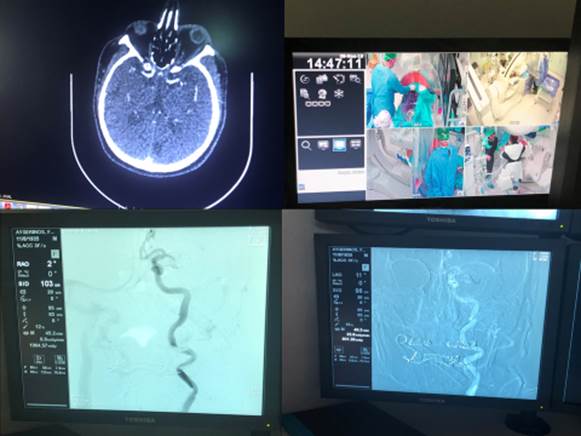

Σε υπερεξειδικευμένα Κέντρα με δυνατότητες επεμβατικής ακτινολογίας καθετηριασμός – διάνοιξη της αποφραχθείσης αρτηρίας με ενδαρτηριακή θρομβόλυση και μηχανική θρομβεκτομή

Εικ. 8α και 8β: ασθενείς με θρομβόλυση και θρομβεκτομή αντίστοιχα στο Νοσοκομείο ΑΧΕΠΑ – Μονάδα Αυξημένης Φροντίδας (Stroke Unit) Α΄ Προπαιδευτικής Παθολογικής Κλινικής Α.Π.Θ και Επεμβατική Ακτινολογία (Αγγειογράφος Ακτινολογικού Εργαστηρίου Α.Π.Θ)